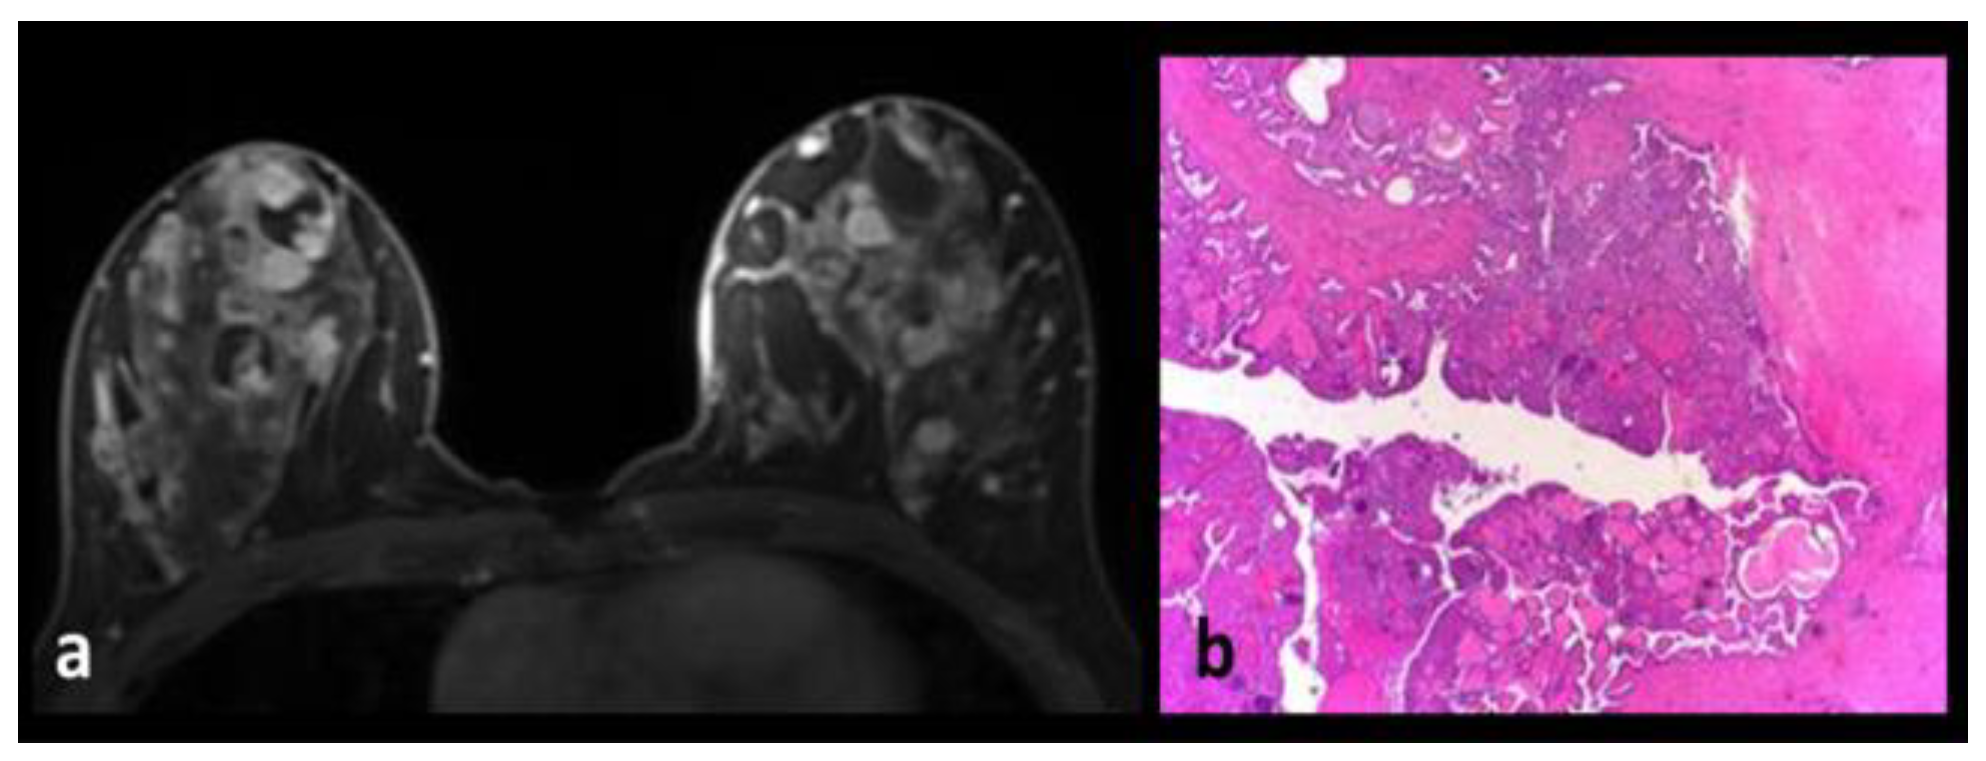

Juvenile Papillomatosis

Intraductal Papilloma-Intraductal Papillomatosis